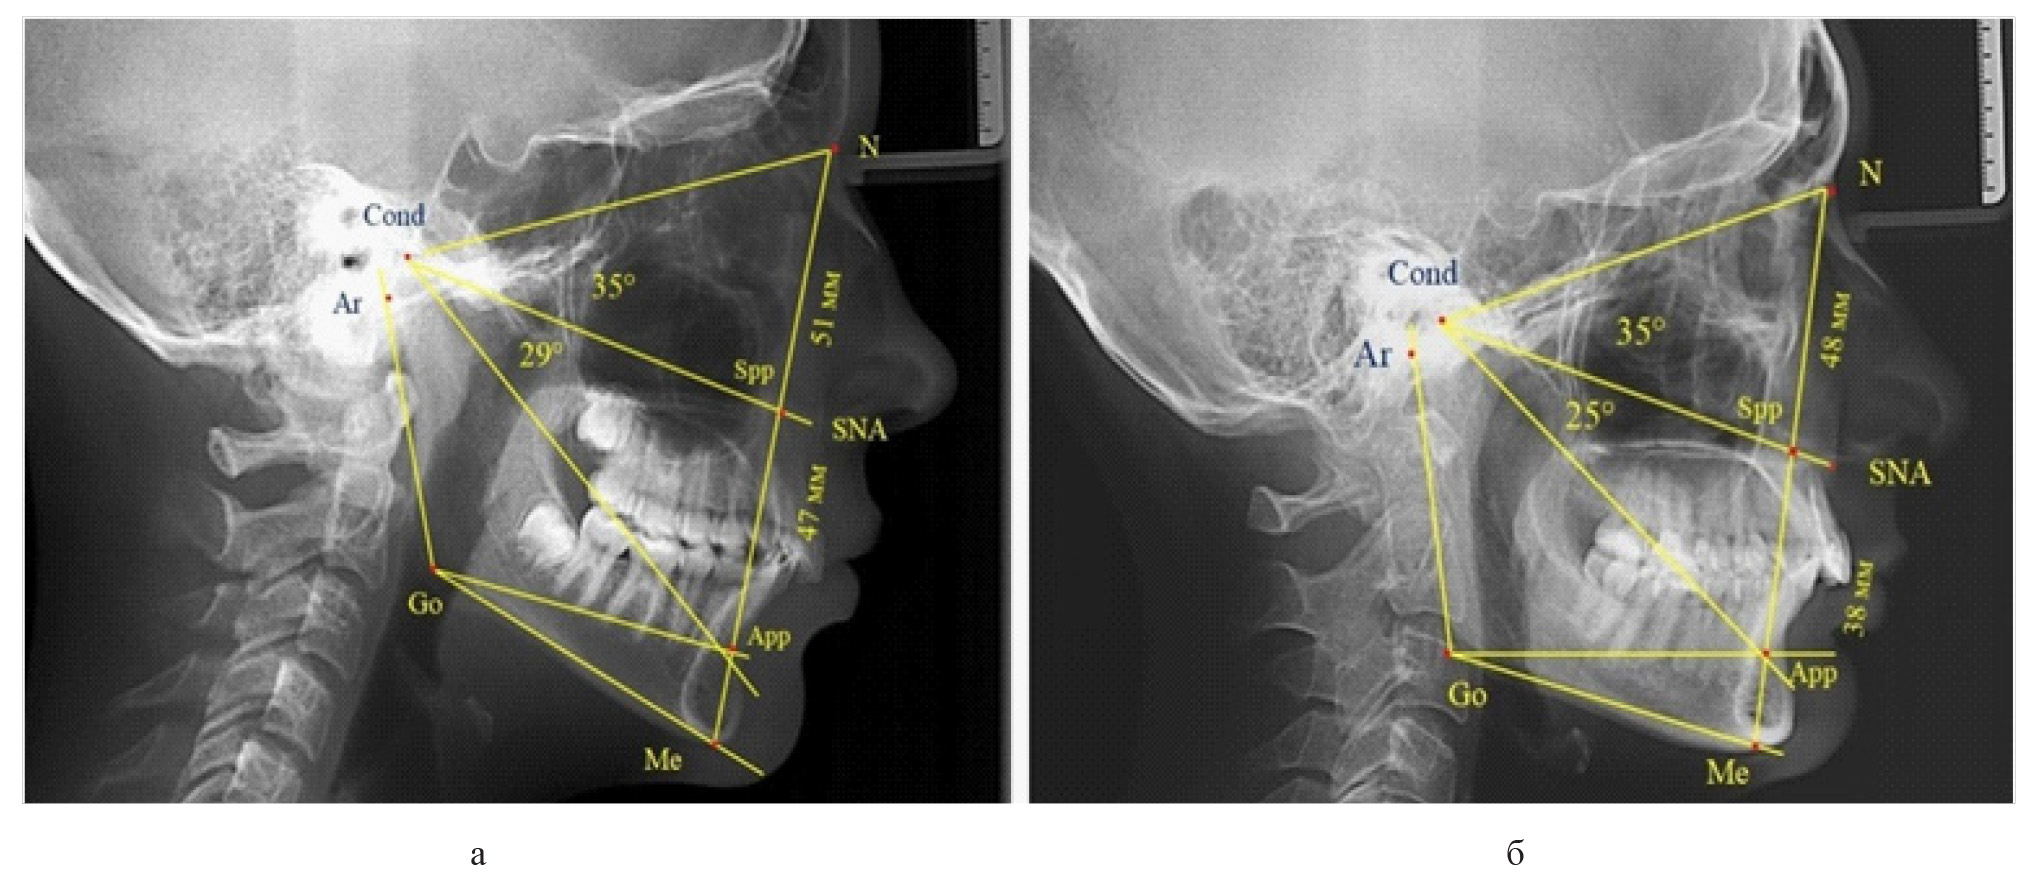

Вертикальная линия передней высоты лица (N-Me), после ее пересечения с линией Cond-SNA, определяла положение точки Spp, при этом вертикаль N-Spp использовалась в качестве оценки высоты назального отдела лица. Продолжение линии Go-Api до пересечения с линией N-Me позволяла определить положение конструктивной точки Арр и оценить линейные размеры гнатической части лица по величине вертикали Spp-Арр (рис. 1).

Рис. 1. Методы оценки основных параметров ТРГ для определения вертикальных размеров лицевого отдела головы

Величина угла назального отдела лица (N-Cond-SNA) в исследуемой группе составила (35,28 ± 0,26)°, а линейные размеры (N-Spp) были (48,82 ± 0,96) мм. Параметры угла гнатической части (SNA-Cond-App) были (29,83 ± 0,54)°, при линейной высоте (49,25 ± 1,31) мм.

Измерения линейных вертикальных параметров показали, что у людей с нейтральным типом роста высота назального отдела составляла (49,53 ± 0,89) мм, а гнатической части – (50,22 ± 0,94) мм и разница в показателях была не достоверной (р ˃ 0,05).

При вертикальным типе роста высота назального отдела составляла (47,79 ± 0,71) мм, а гнатической части – (46,82 ± 0,66) мм.

Для горизонтального типа роста характерна высота назального отдела (47,75 ± 0,75) мм, а гнатической части – (46,49 ± 0,58) мм.

Признаки снижения высоты назального отдела вплоть до уровня горизонтального патологического типа при физиологической окклюзии были определены у 10 человек [(17,86 ± 5,11) %]. При этом параметры гнатического отдела соответствовали физиологической норме либо физиологическому горизонтальному типу (рис. 4).

Рис. 4. Варианты ТРГ с укороченными размерами носового отдела и оптимальными (а) и укороченными (б) размерами гнатической части